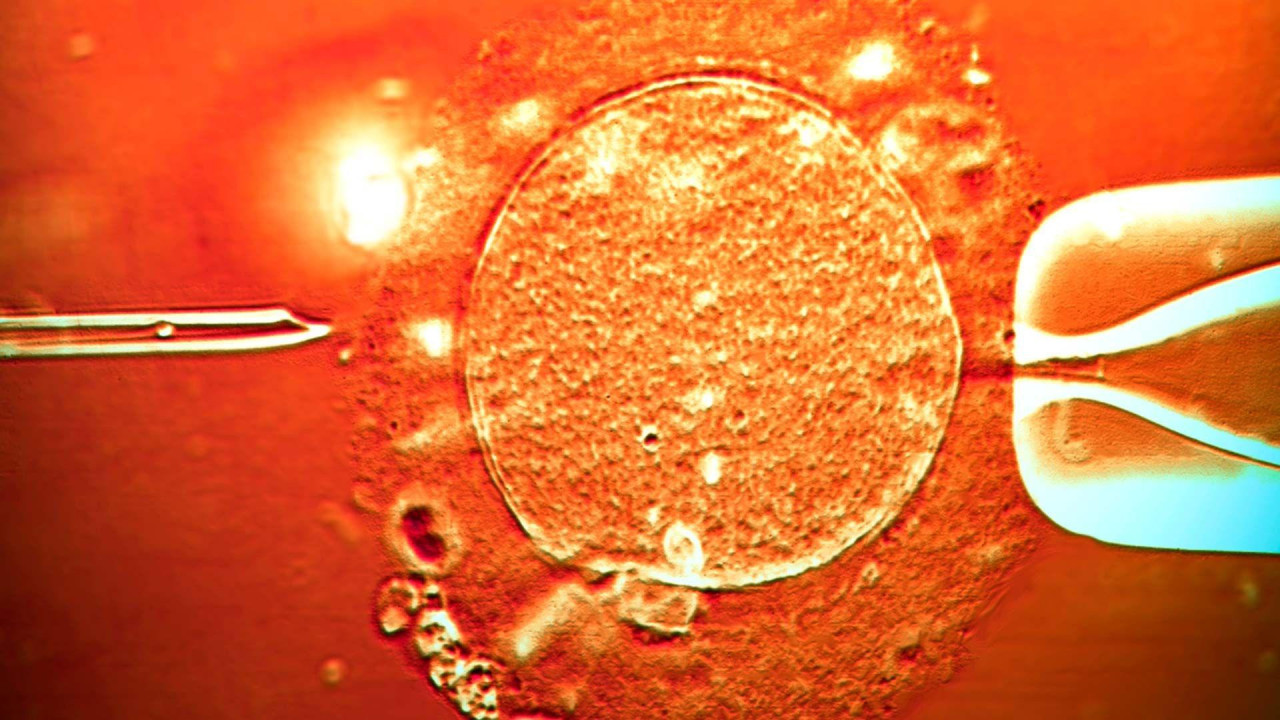

Color light micrograph of a micro-needle (left) about to inject human sperm into a human egg cell being held in place by a pipette . IVF treatment.